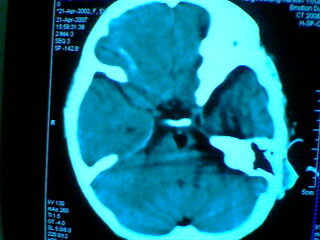

发热2天 无咳嗽咳痰 抽搐数次 现浅昏迷

其它层面无异常表现 故未上传

脂肪瘤?皮样囊肿?表皮样囊肿?

考虑 脑干脂肪瘤可能性大

位于中线部位,多考虑脂肪瘤

基底池脂肪瘤。

考虑:左侧桥小脑角池、基底池表皮样囊肿可能性大。

左侧桥小脑角池表皮样囊肿可能性大,部分突入桥前池,引起脑干受压